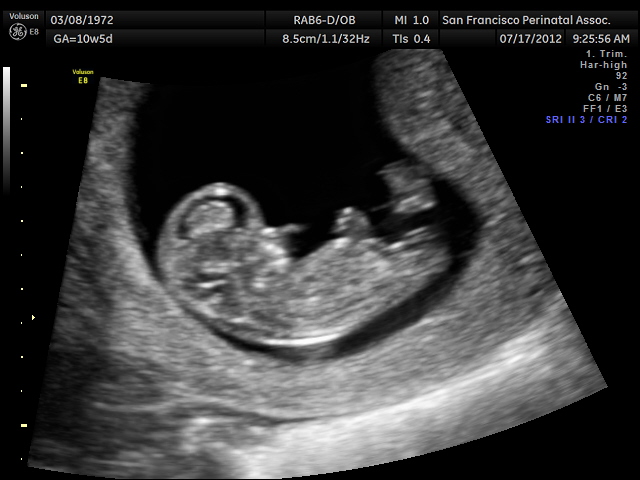

Rose's Ultrasound: 11 weeks, 2 days

This photo from my CVS ultrasound today. Although by last period, I am 10w5d, by size of baby, I am 11w2d. I know this is early, but I have seen all three of my boys by 12 weeks without any doubt, and to me, this looks like three lines. I have two other photos with a straight fork as well. Is it possible?